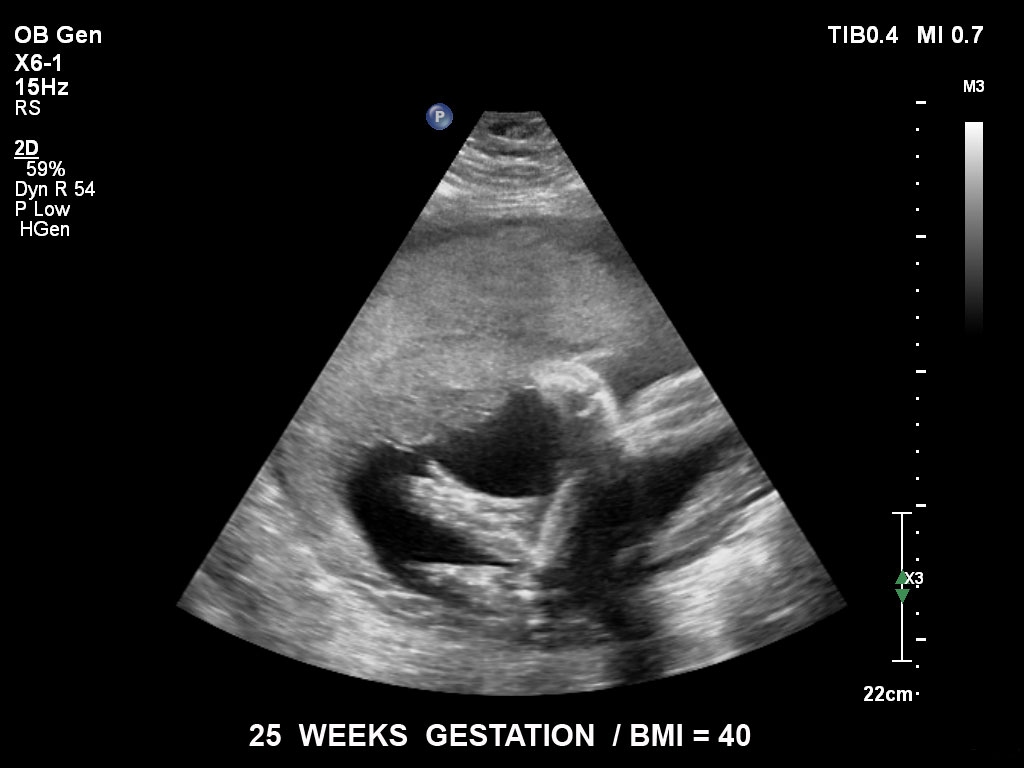

• C5-1 PureWave-Breitband-Convex-Schallkopf für hohe Eindringtiefen in der Gynäkologie und der Geburtshilfe, für Patientinnen mit Schwangerschaftsdiabetes oder vorzeitigem Blasensprung

• X6-1 PureWave-xMATRIX Schallkopf für diagnostische Anforderungen, die über die 2D-Bildgebung hinausgehen, setzt mit PureWave neue Maßstäbe u.a. bei der Live-Volumenbildgebung und Live-Bildgebung in zwei Ebenen gleichzeitig